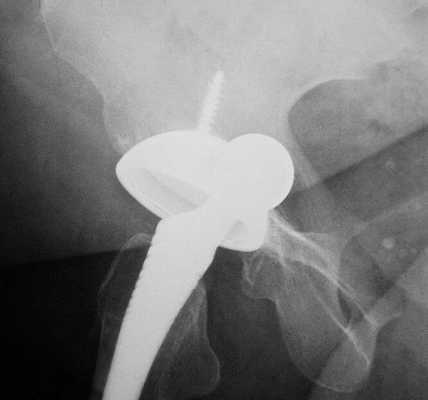

(Слева) МР-артрография в режиме Т1ВИ FS, коронарный срез: визуализируется неоднородное скопление контрастного препарата, распространяющееся через разорванную подвздошно-бедренную связку за пределы суставной капсулы.

(Справа) Артрография, передне-задняя проекция: определяется небольшой затек контрастного препарата через подвздошно-бедренную связку, обусловленный тем, что после артроскопической операции дефект суставной капсулы не был закрыт. Пациент ощущал нестабильность сустава.